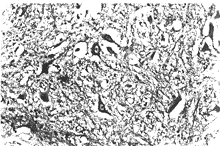

急性壞死出血性腦脊髓炎病理學發現有獨特之處,在大腦切片上,可見一側或兩側大腦半球白質被破壞至幾乎液化的程度。主要影響雙側額葉。受累組織呈粉紅色或灰黃色夾雜多發性小出血斑點。相同的改變也常見於腦幹和小腦臂,偶見於脊髓。組織學檢查發現廣泛的小血管和血管周圍腦組織壞死,伴有大量細胞浸潤、多發性小灶出血和不同程度的腦膜炎性反應,病損分布於血管周圍的病理特點與播散性腦脊髓炎相似,不同之處是增加了廣泛壞死和大腦半球內病損傾向形成大的病灶血管的病灶導致纖維蛋白滲出至血管壁和周圍組織。同樣的壞死性病損可發生於脊髓,而表現為暴發性脊髓炎是完全可能的,但這一推測難以得到病理學的證實。

本病是一種罕見的發展迅速而兇險的疾病,常是敗血性休克、過敏反應(哮喘等)的一種嚴重併發症。可能是一種由於免疫複合物沉積和補體激活所致的超急型急性播散性腦脊髓炎。病變的特點為腦腫脹伴白質點狀出血,與腦脂肪栓塞頗相似。鏡下變化特點為小血管(小動脈、小靜脈)局灶性壞死伴周圍球形出血;血管周圍脫髓鞘伴中性粒細胞、淋巴細胞、巨噬細胞浸潤;腦水腫和軟腦膜炎。與急性播散性腦脊髓炎之區別在於本病的壞死較廣泛,急性炎性細胞浸潤以及血管周圍出血較明顯。病變在大腦半球和腦幹較多見,呈灶性分布。